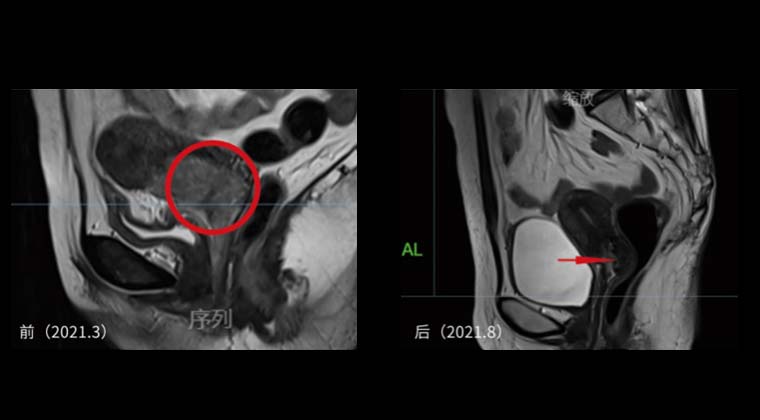

Сравнение до и после лечения показывает значительную регрессию опухоли и её исчезновение.

Рисунок 1: План лечения внешним облучением + брахитерапией с дистанционным введением источника

Рисунок 2 слева: До лечения

Рисунок 2 справа: После лечения